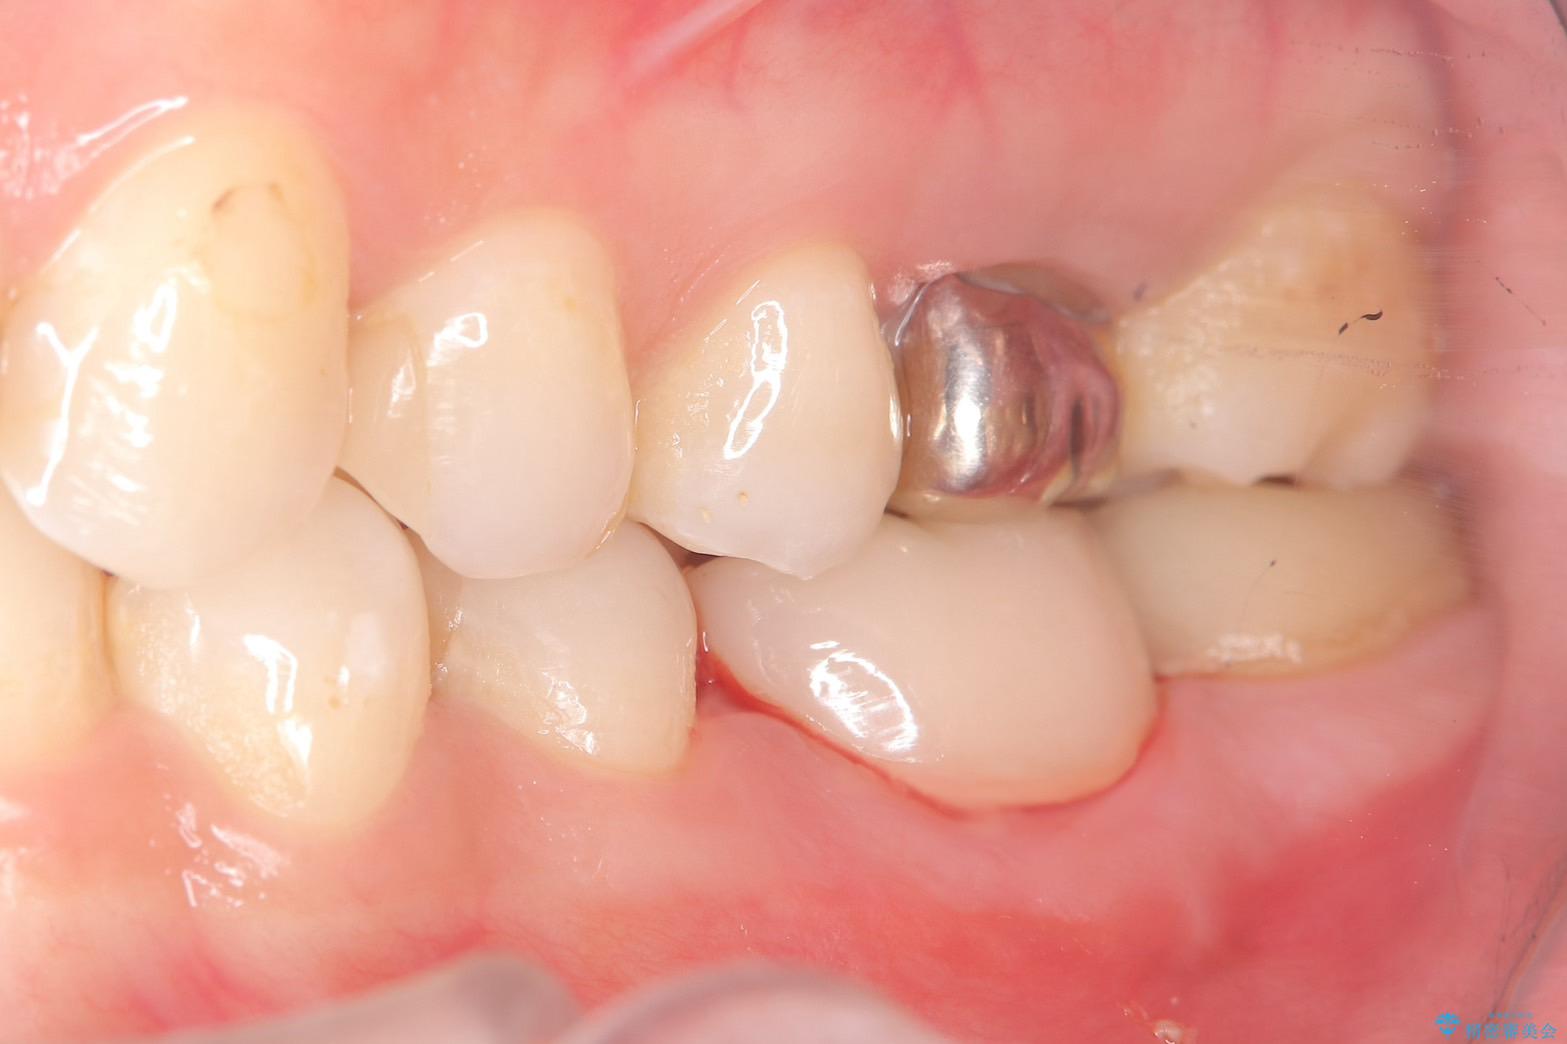

- 主訴:左下6番目の歯の周りが痛くなり、他院で診てもらったが抜歯と言われてしまった。ネットで歯牙移植というものを知りやっている医院を探している。

左下6番目の歯の周りに大きく透過像を認め、再根管治療後の予後が良くない可能性が大きく当院でも抜歯適用歯と説明しました。欠損部に対しインプラント治療や歯牙移植(左下の親知らずの移植)、ブリッジを提案し、歯牙移植を行うこととなりました。